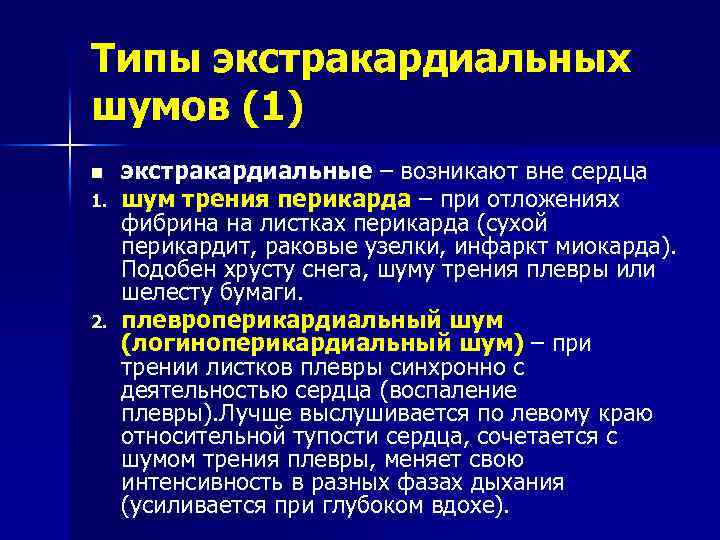

Типы экстракардиальных шумов (1) n 1. 2. экстракардиальные – возникают вне сердца шум трения перикарда – при отложениях фибрина на листках перикарда (сухой перикардит, раковые узелки, инфаркт миокарда). Подобен хрусту снега, шуму трения плевры или шелесту бумаги. плевроперикардиальный шум (логиноперикардиальный шум) – при трении листков плевры синхронно с деятельностью сердца (воспаление плевры). Лучше выслушивается по левому краю относительной тупости сердца, сочетается с шумом трения плевры, меняет свою интенсивность в разных фазах дыхания (усиливается при глубоком вдохе).